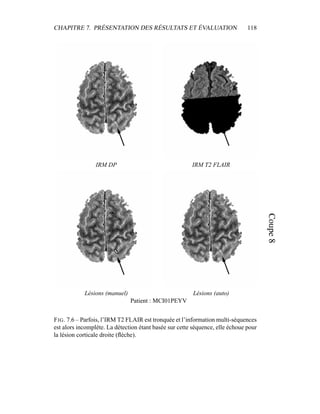

c’est donc sur elle que portera l’analyse lors de la segmentation en tissus et de la

présentation du modèle de volume partiel. Les autres modalités seront utilisées a

posteriori.

4.4 Segmentation en tissus.

4.4.1 Algorithme